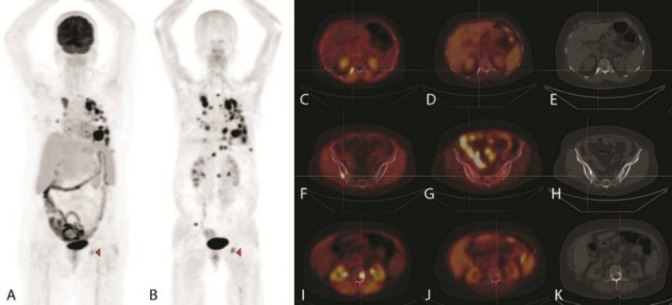

Results: Physiologic distribution of [68Ga]-Ga-FAPI-46 was observed in the liver, blood pool and kidneys, whereas no tracer uptake was noted in the brain and heart. The mean liver SUVmax for [68Ga] Ga-FAPI-46 was 1.5±0.1 which was lower than that noted for [18F]-FDG PET/CT (2.9±0.2). Likewise, the mean blood pool SUVmax value for [68Ga]-Ga-FAPI-46 was lower than [18F]-FDG PET/CT (1.7±0.1 versus 2.0±0.1). [68Ga]-Ga-FAPI-46 PET/CT demonstrated higher tracer uptake in the lesions detected in the brain, bone, internal mammary and lymph nodes in 4/12 patients. The overall lesions detections and the mean SUVmax values did not differ significantly between the two techniques. On the other hand, [68Ga]-Ga-FAPI-46 demonstrated higher mean TBRmax than [18F] FDG PET/CT particularly for lesions detected in kidneys, chest wall, mediastinum, and musculoskeletal lesions. However, both techniques offered identical TNM staging.

Conclusion: The findings of this preliminary study demonstrated that [68Ga]-Ga-FAPI-46 and [18F]-FDG PET/CT offered identical disease staging in the breast cancer patients. [68Ga]-Ga-FAPI-46 showed lower liver and blood pool uptake and an enhanced tumor-to-background ratio, thereby suggesting its potential for improved lesions detection. This may open opportunity for emerging FAP based radioligand for therapeutic applications in advanced stage breast cancers. However, this needs validation in a larger number of patients.